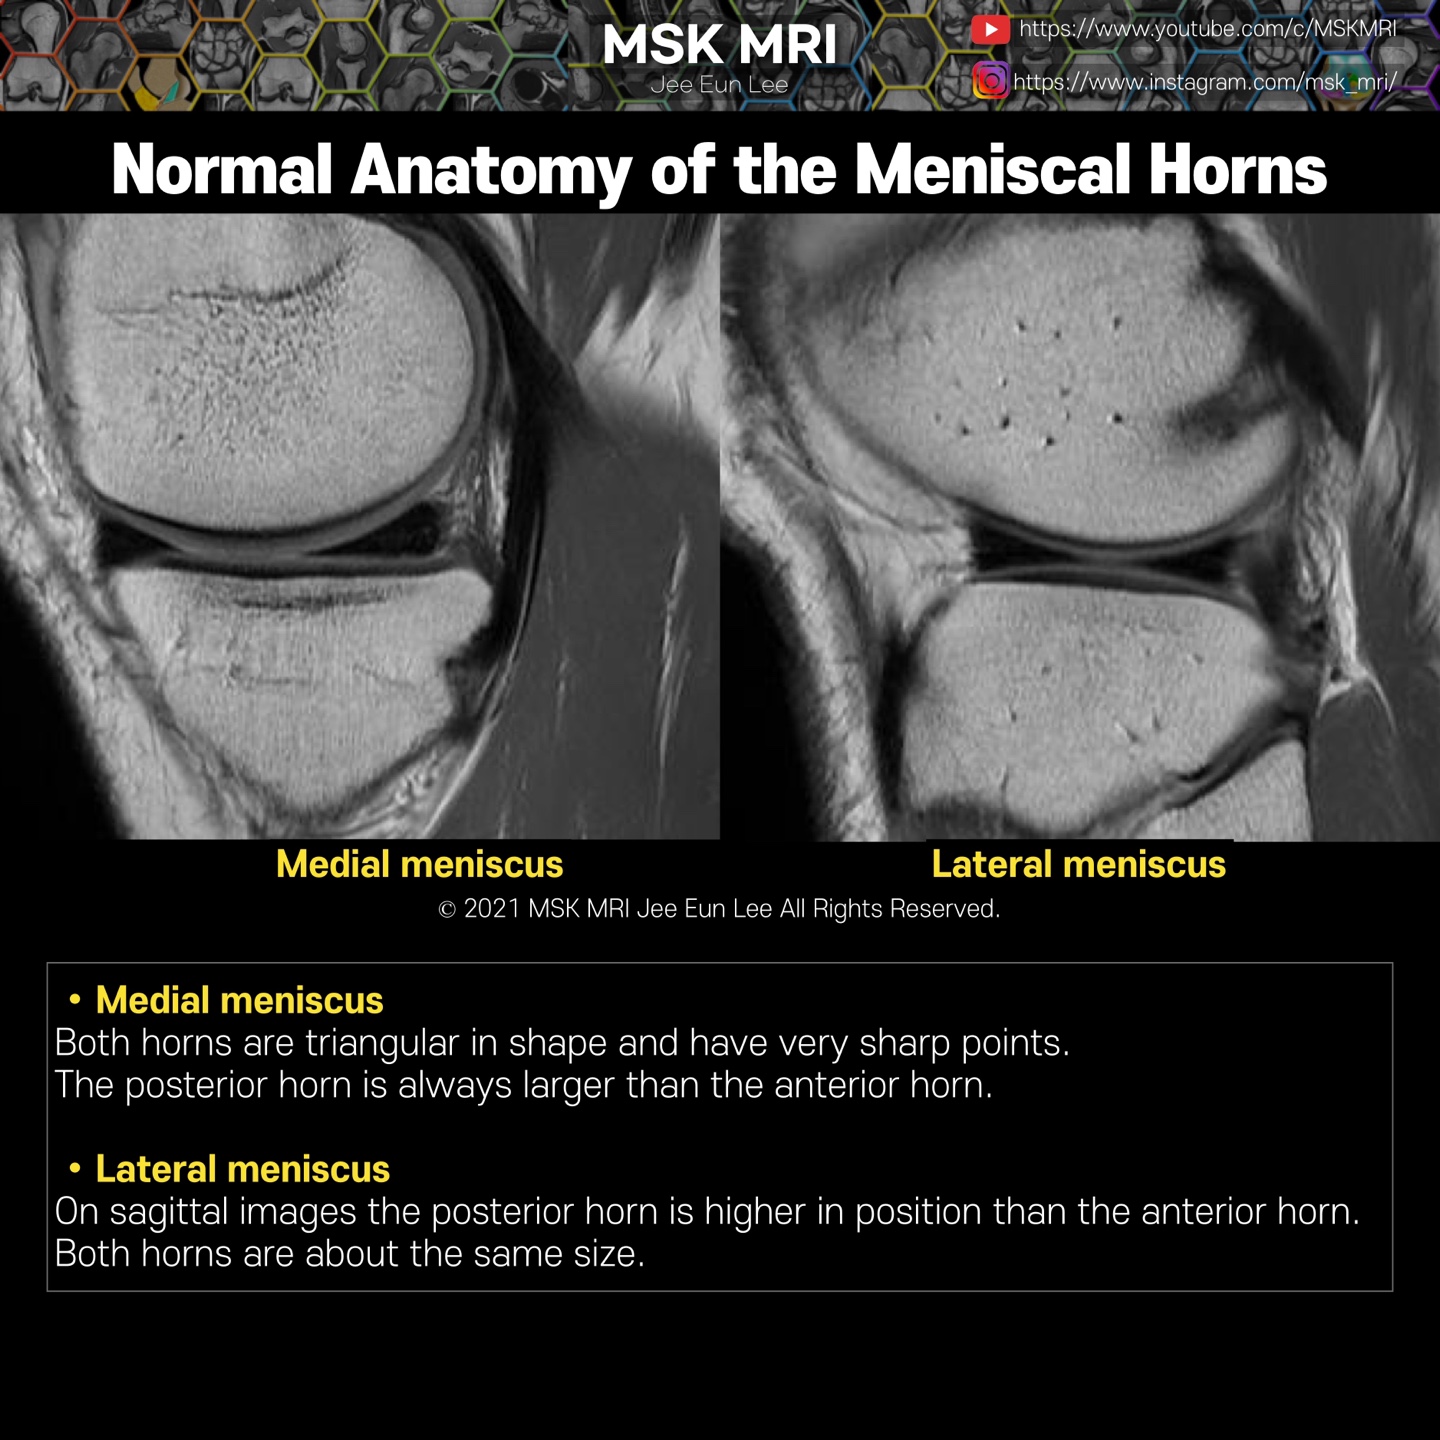

* MM: The larger, more open C- shaped medial meniscus increases in width from anterior to posterior, resulting in a larger posterior horn compared with the anterior horn when viewed in cross-section.

* LM: The more circular lateral meniscus maintains a relatively constant width, resulting in the anterior and posterior horns being nearly equal in size in cross-section